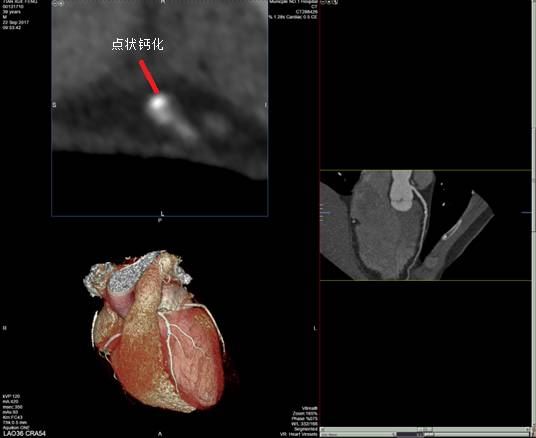

通过冠脉探针可以显示管腔横截面,以便更好的观察斑块形态。通常在VR项可以显示探针的位置,以此点为中心,向上、向下各显示7个断层,每个断层1 mm,加上所选取的一层,共显示15 mm长的冠状动脉管腔横截面,冠脉探针与CPR相结合,能更精确的判断冠脉管腔狭窄程度。而探针显示的某个特点也可以初步判断斑块的稳定性,如点状钙化、指环征等。

■ 钙化病变

对于严重钙化病变,由于CTA处理后会出现伪影,无法真实了解管腔的狭窄程度,所以冠脉CTA作为判定标准会出现偏差,一般认为钙化斑块较大时不能将冠脉CTA作为评价冠脉狭窄的标准。